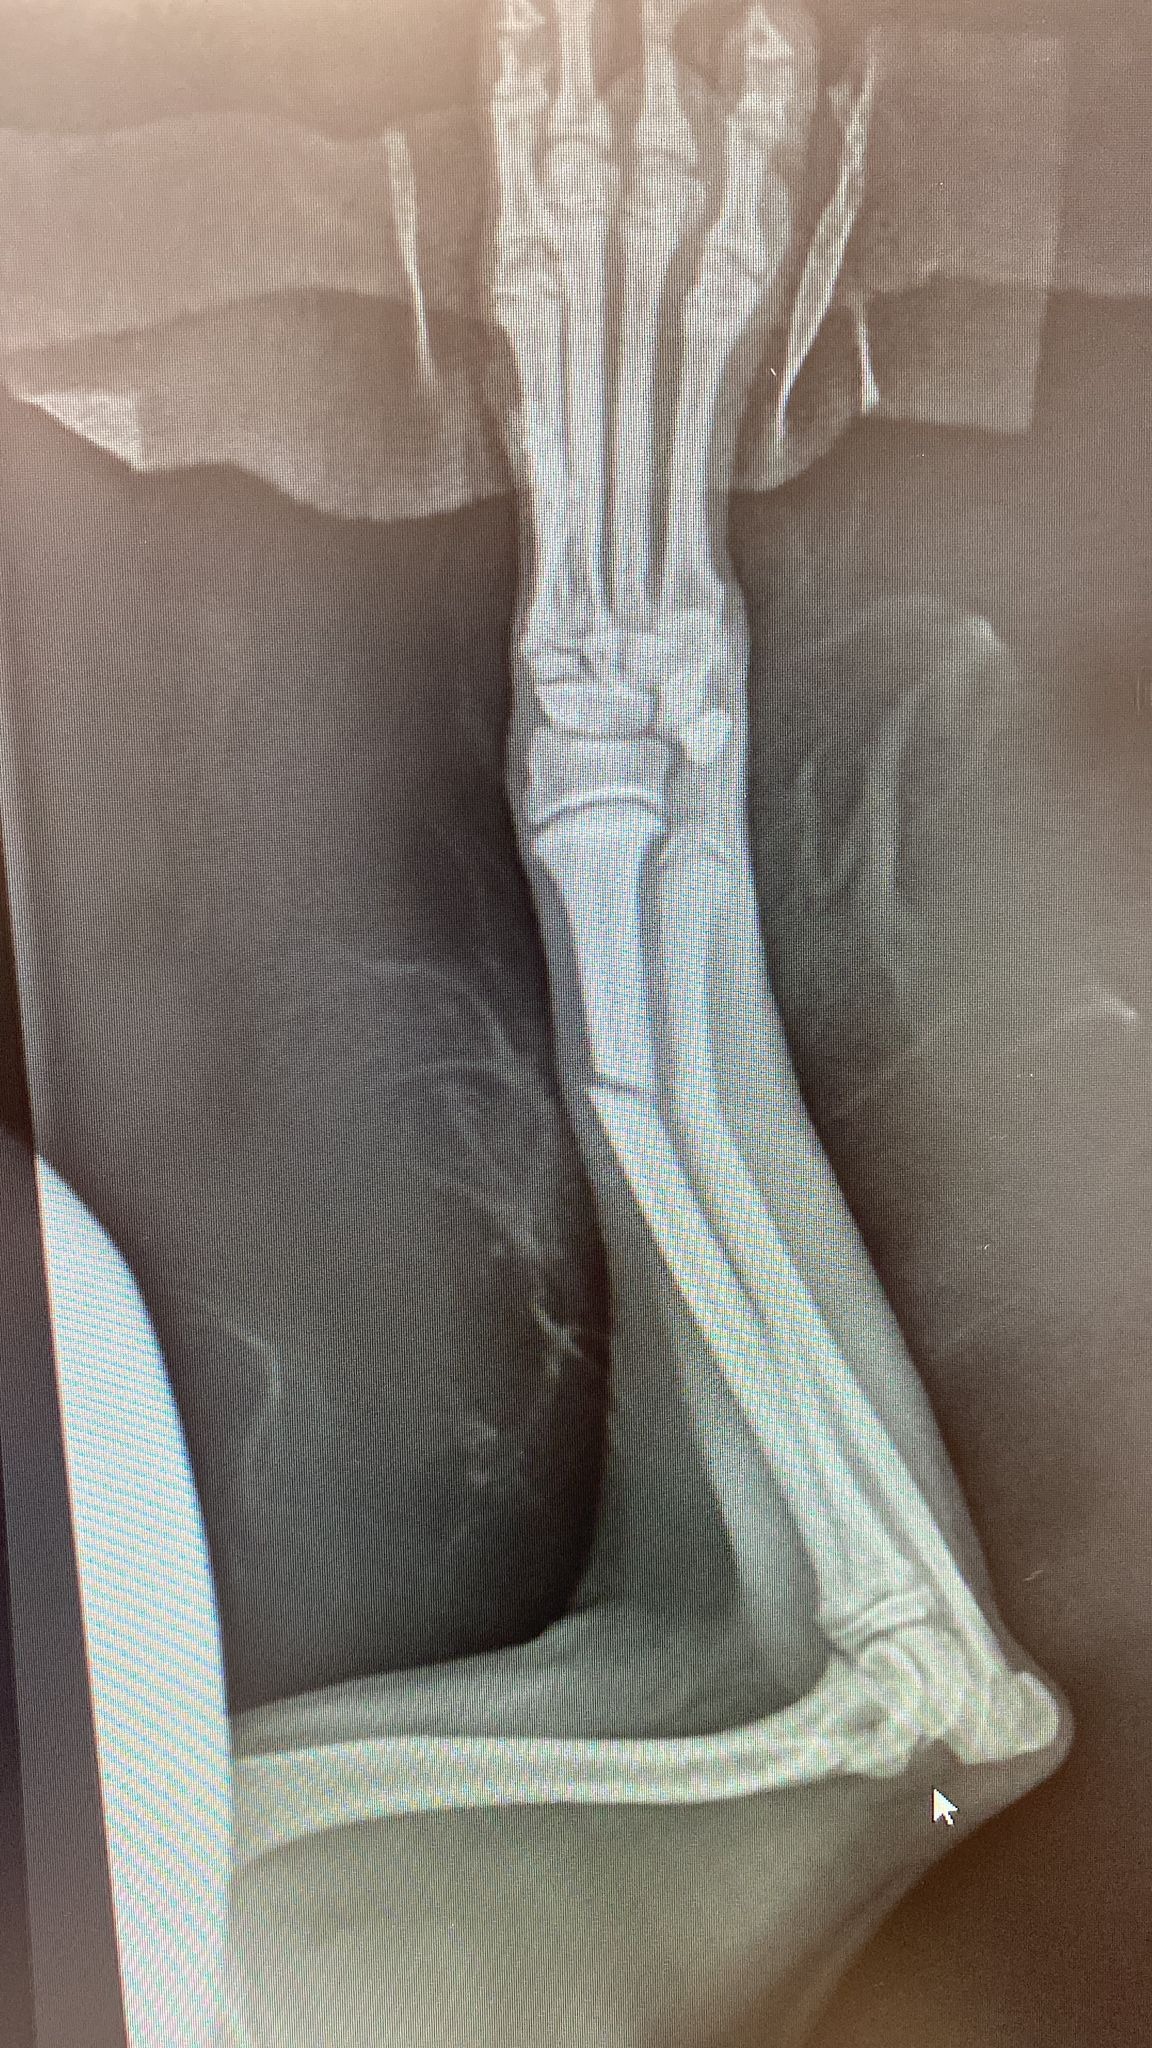

Little snoop dog arrived, he is just a young 12 week old puppy who is loving life in foster with some of his friends. Snoop had an unfortunate accident after jumping from a small box holding his toys. A freak accident or his bones are just not strong enough at the moment - we don't know.

What we do know is, we rushed him straight in to our vets and he had surgery the very same afternoon.

Snoop is now sporting an External Fixator and is having regular checks with the vets to ensure all is going well. We have also added supplements to his diet to strengthen his bones and aid his recovery.